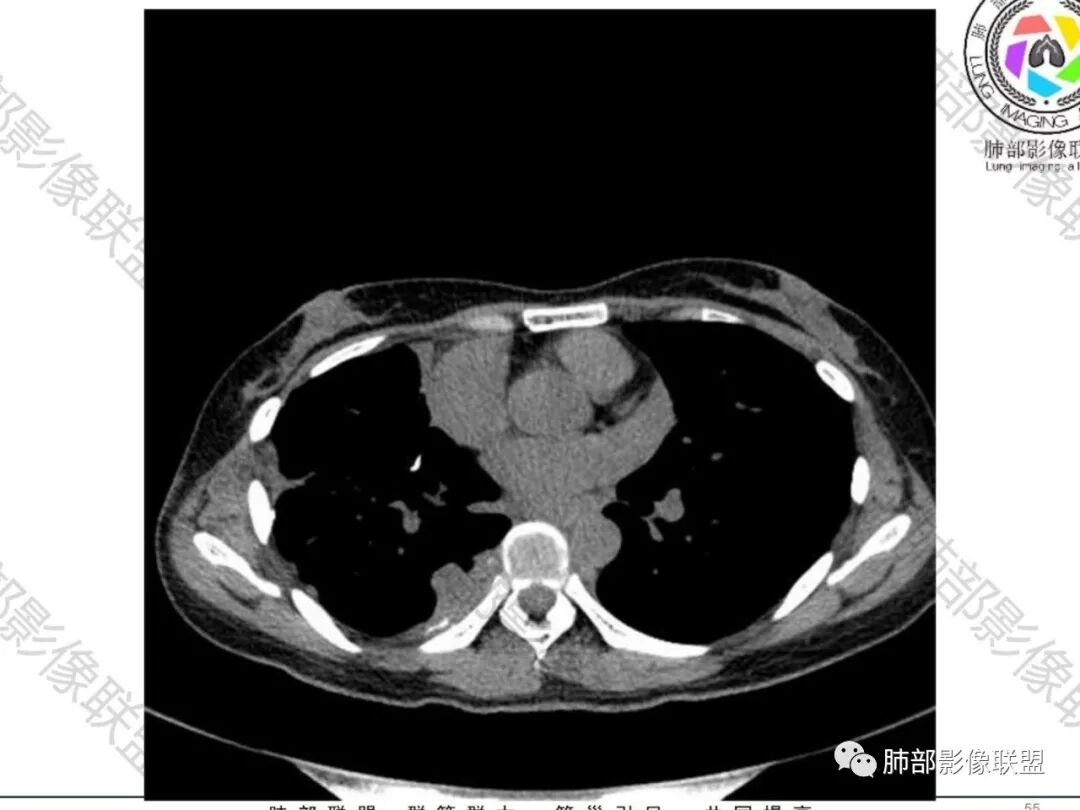

一切∮随缘:双侧胸廓塌陷,以右侧为主,右侧肋间隙狭窄,双肺上叶及右肺下叶胸膜下多发不规则肿块,密度不均匀,内部可见条片状,不规则钙化影,部分钙化不密实,双肺多发纤维索条影,似陈旧性病灶,双侧胸水,临床年轻女性,无感染症状,考虑考虑结核淀粉样变,转移性钙化,弥漫性肺骨化病。

王秀仙:双肺多发条索状及结节状病灶,部分钙化,边界清晰,双侧纵膈胸膜及双侧胸膜可见结块状及弧形软组织肿块,内见多发钙化灶,右侧胸腔塌陷,考虑结核伴淀粉样变性。鉴别胸膜间皮瘤。

丽:双肺散在索条及条片状高密度影,边界清晰,部分实变内可见钙化,支气管管壁增厚,双肺胸膜局限性增厚伴钙化,部分肋骨密度增高,首先考虑结核并淀粉样变性,鉴别转移性钙化,肿瘤样钙质沉着症,胸膜间皮瘤。

傅昌瑜:青年女性,咳嗽胸痛2月,偶有血痰。双肺上叶多发不规则肿块,密度不均匀,内部可见点状、条片状钙化影,右上肺病灶空洞,壁厚薄不均,见壁结节,与支气管关系不清,两侧胸膜增厚,见多发结节,部分结节边缘膨隆明显,结节内亦有多发钙化。上述改变常见于结核、尘肺、钙化性转移等疾病。有膨隆感的结节考虑转移可能性大。

尘缘:青年女性,痰中带血,胸痛2月,无发热盗汗,实验室检查,有贫血,总蛋白降低,血沉情况未知,肿标基本正常。影像表现:双上肺小叶间隔增厚,双侧胸膜广泛不规则增厚,胸膜下多发肿块伴不规则钙化,右侧肋骨破坏。纵隔淋巴结肿大不明显,双肺门淋巴结肿大,部分融合,分析思路:一、感染性病变,1、结核,青年女性,胸膜增厚,多发肿块伴钙化,有咳嗽胸痛,痰中带血,要考虑,但无结核中毒症状,病史仅两月却钙化太明显,肺内没有明显树芽征,存疑,2、其他感染,无炎性指标支持,白细胞不高,可能性小。二、非感染性病变,1、尘肺,胸膜增厚,钙化,胸膜下钙化性肿块,要考虑,但肺内无粉尘结节,无职业史,可能小。2、转移性钙化,无肾脏病史,无血清钙磷代谢异常指标支持,肺内间质无钙沉积改变,基本排除。三、肿瘤性病变,1、肺癌伴转移,双上肺有小叶间隔增厚,双肺门有淋巴结肿大,要考虑,但青年女性,病史两月,钙化太多太广泛,肿标基本正常,可能性小。2、骨肉瘤转移。15-30岁青年人,是骨肉瘤高发年龄,肺内多发成骨样钙化转移灶,双上肺小叶间隔增厚符合癌淋样表现,右侧肋骨破坏,要高度怀疑,需要详细询问病史及手术史。3、软骨来源肿瘤伴肺内转移,右侧肋骨虽有破坏,但无明显软骨样破坏及钙化。可能小。4、其他肿瘤伴转移,青年女性,其他恶性肿瘤能广泛发生钙化性转移的可能性小。综上所述:骨肉瘤伴右侧肋骨及胸膜转移,胸膜下转移,肺内癌淋可能最大,结核不完全除外,下一步需要,仔细询问病史,如果有骨肉瘤史,则基本确诊,如果没有,需要进一步问询呼吸系统症状,病程,以前的影像对照,了解肾脏情况,查血清钙磷指标。

右肺体积缩小,上叶见空洞影

内壁较光滑,但有壁结节

上叶内多个结块,边缘有膨隆,内有钙化灶

钙化灶密度较高,环形/结节状

胸膜及附近肺内见多发结节/斑块

密度类似

边缘膨隆